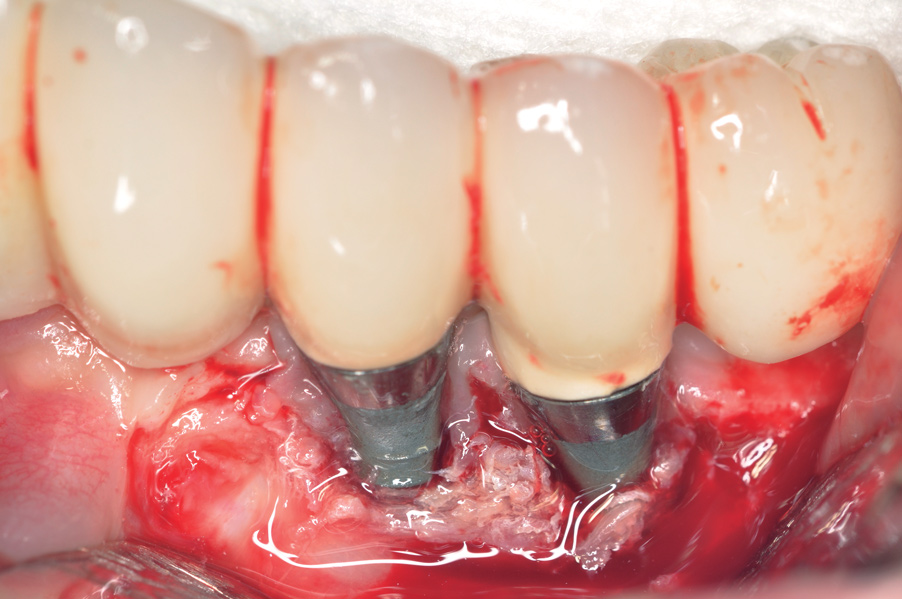

Dental implants have revolutionized the way in which clinicians treat and restore partially and fully edentulous patients and have demonstrated success for managing a broad range of clinical dilemmas. While implants have been highly predictable and have achieved long-term success, they are not immune from complications associated with improper treatment planning, poor surgical and prosthetic execution, material failure, and inadequate or infrequent maintenance. Among these problems are the biologic complications of peri-implant mucositis and peri-implantitis, which are inflammatory conditions in the soft and/or hard tissues surrounding dental implants (Figure 1 through Figure 4).1,2

Fig 5. Clinical view of implants depicting suggested bone loss. Plaque was present throughout, and the distal-most implant had substantial purulent exudate.

Figure 5

Fig 6. From a more anterior view, it was apparent that the labial positioning of these implants was outside the alveolar housing.

Figure 6

Fig 7. Radiographic image of the area suggesting severe bone loss around the dental implants.

Figure 7

Studies have demonstrated that much like teeth, dental implants have a certain biologic dimension established following their healing after surgery and much of this understanding comes from evidence obtained from animal studies.18,19 However, in a seminal article on implant placement, Salama et al20 further highlighted the concept of bone surrounding an implant. A violation to the dimension of bone present in any of the buccal-palatal, mesial-distal, or apical-coronal directions will lead to bone loss (Figure 5 through Figure 7). This relates to the blood supply necessary to maintain the bone surrounding a dental implant. If an implant is placed in a position in which the minimal bone dimensions are not respected, crestal loss can be anticipated. While this may represent a contained lesion and remain static, it may not always be the case. In implants designed with a surface roughened to the top, suboptimal plaque control can lead to ongoing bone loss, because the exposed roughened surface is challenging to clean and will act as a plaque-retentive feature.21

Poor implant positioning can also compromise the patient’s plaque-control efforts. While the location of the bone may not allow for optimal implant placement, unintended negative consequences can result from the prosthesis superstructure impeding the patient’s attempts at controlling plaque. Typically, the use of pink porcelain or composite to close apical or interproximal spaces caused by restoration of a malposed implant will not allow patient access for adequate homecare.